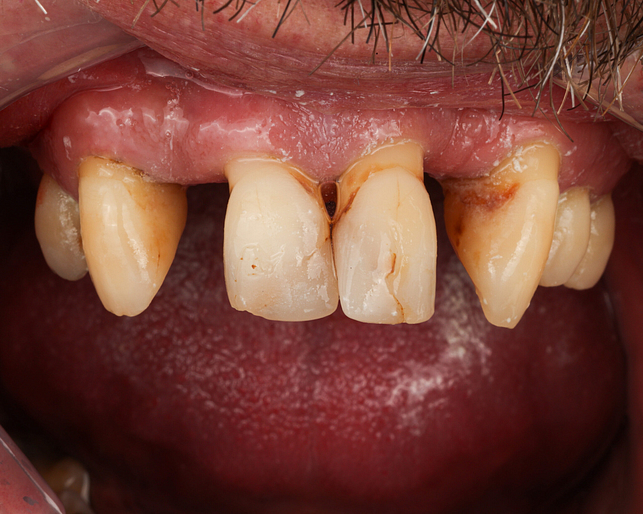

Before